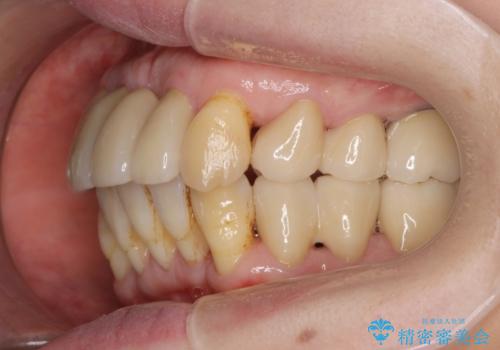

- 重度の歯周病に罹患しており、他院で「多数の歯を抜歯したのち、入れ歯を入れるしかない。」と言われ、入れ歯以外の方法がないか相談のため来院されました。

重度の歯周病で多数の歯を残せない問題、歯並び・噛み合わせの問題、欠損の問題、と多数の大きな問題が認められました。

インプラント治療に加え、歯周病に対しての再生治療や歯周ポケットの除去を行う歯周外科、矯正治療、と必要な治療は多岐に渡りましたが、最終的に安定した噛み合わせを得られたとともに、清掃のしやすい口腔内環境を確立できました。